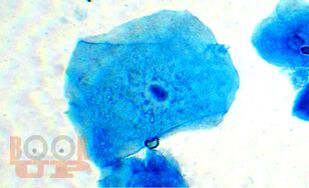

В монографии представлены новые данные об исследовании мочи и желудочного содержимого. Впервые разработаны способы диагностики половой принадлежности мочи по различиям в содержании ядросодержащих и безъядерных клеток и достоверного установления наличия желудочного содержимого на вещественных доказательствах и во внешней среде. В работе приведены результаты исследований о влиянии различных факторов на клеточный состав мочи и на выявляемость желудочного содержимого.